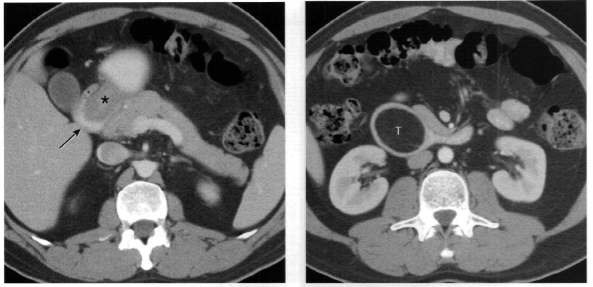

Homem, 57 anos, história de pancreatite crônica

Pseudoaneurisma da artéria mesentérica superior

Separação da camada média e da adventícia na parede da artéria (diferente do aneurisma, que seria a dilatação das três paredes do vaso). Pode ocorrer por aterosclerose, trauma, inflamação (como neste caso).

Pode estar associado à ruptura (pseudoaneurisma tem risco muito maior que de um aneurisma).